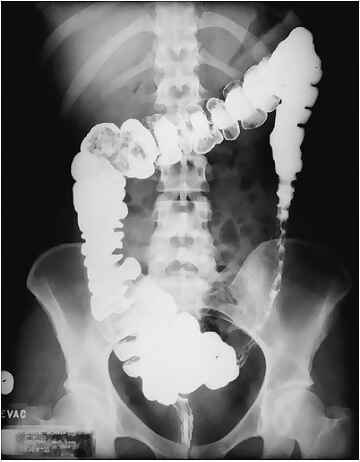

Колит – воспаление слизистой оболочки толстого кишечника. Часто воспаление толстой кишки сопровождается воспалением слизистой желудка (гастрит) и тонкой кишки (энтероколит). При обширных воспалительных процессах желудочно-кишечного тракта необходимо проводить комплексное лечение энтероколита и колита.

В основе диагностики лежит осмотр больного, история болезни, лабораторные исследования (анализы крови, анализ кала на наличие инфекций и яйца гельминтов), УЗИ брюшной полости, ректороманоскопия, и другие инструментальные методы.